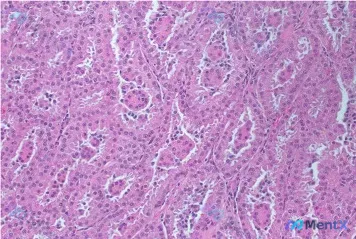

最近看到一例切除肾上腺肿瘤的H&E染色切片,整理了一下读片思路和大家分享。 基本信息 - 标本来源:切除的肾上腺肿瘤 - 染色方法:Hematoxylin and eosin (H&E) - 视野:高倍镜,标尺 300μm 镜下关键特征 1. 组织架构:可见明显的管状/腺管状排列模式,部分管腔不规则...